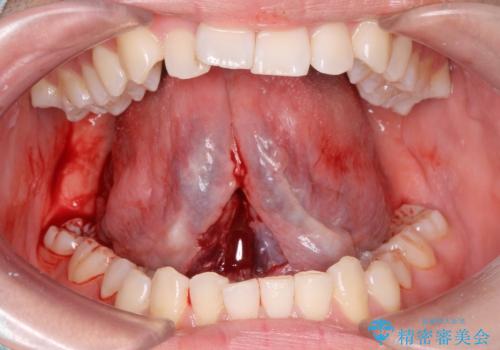

- 英語の練習をしていて舌が動かしにくいとの事で来院。

舌小帯切除術を行い舌の可動域を広げました。